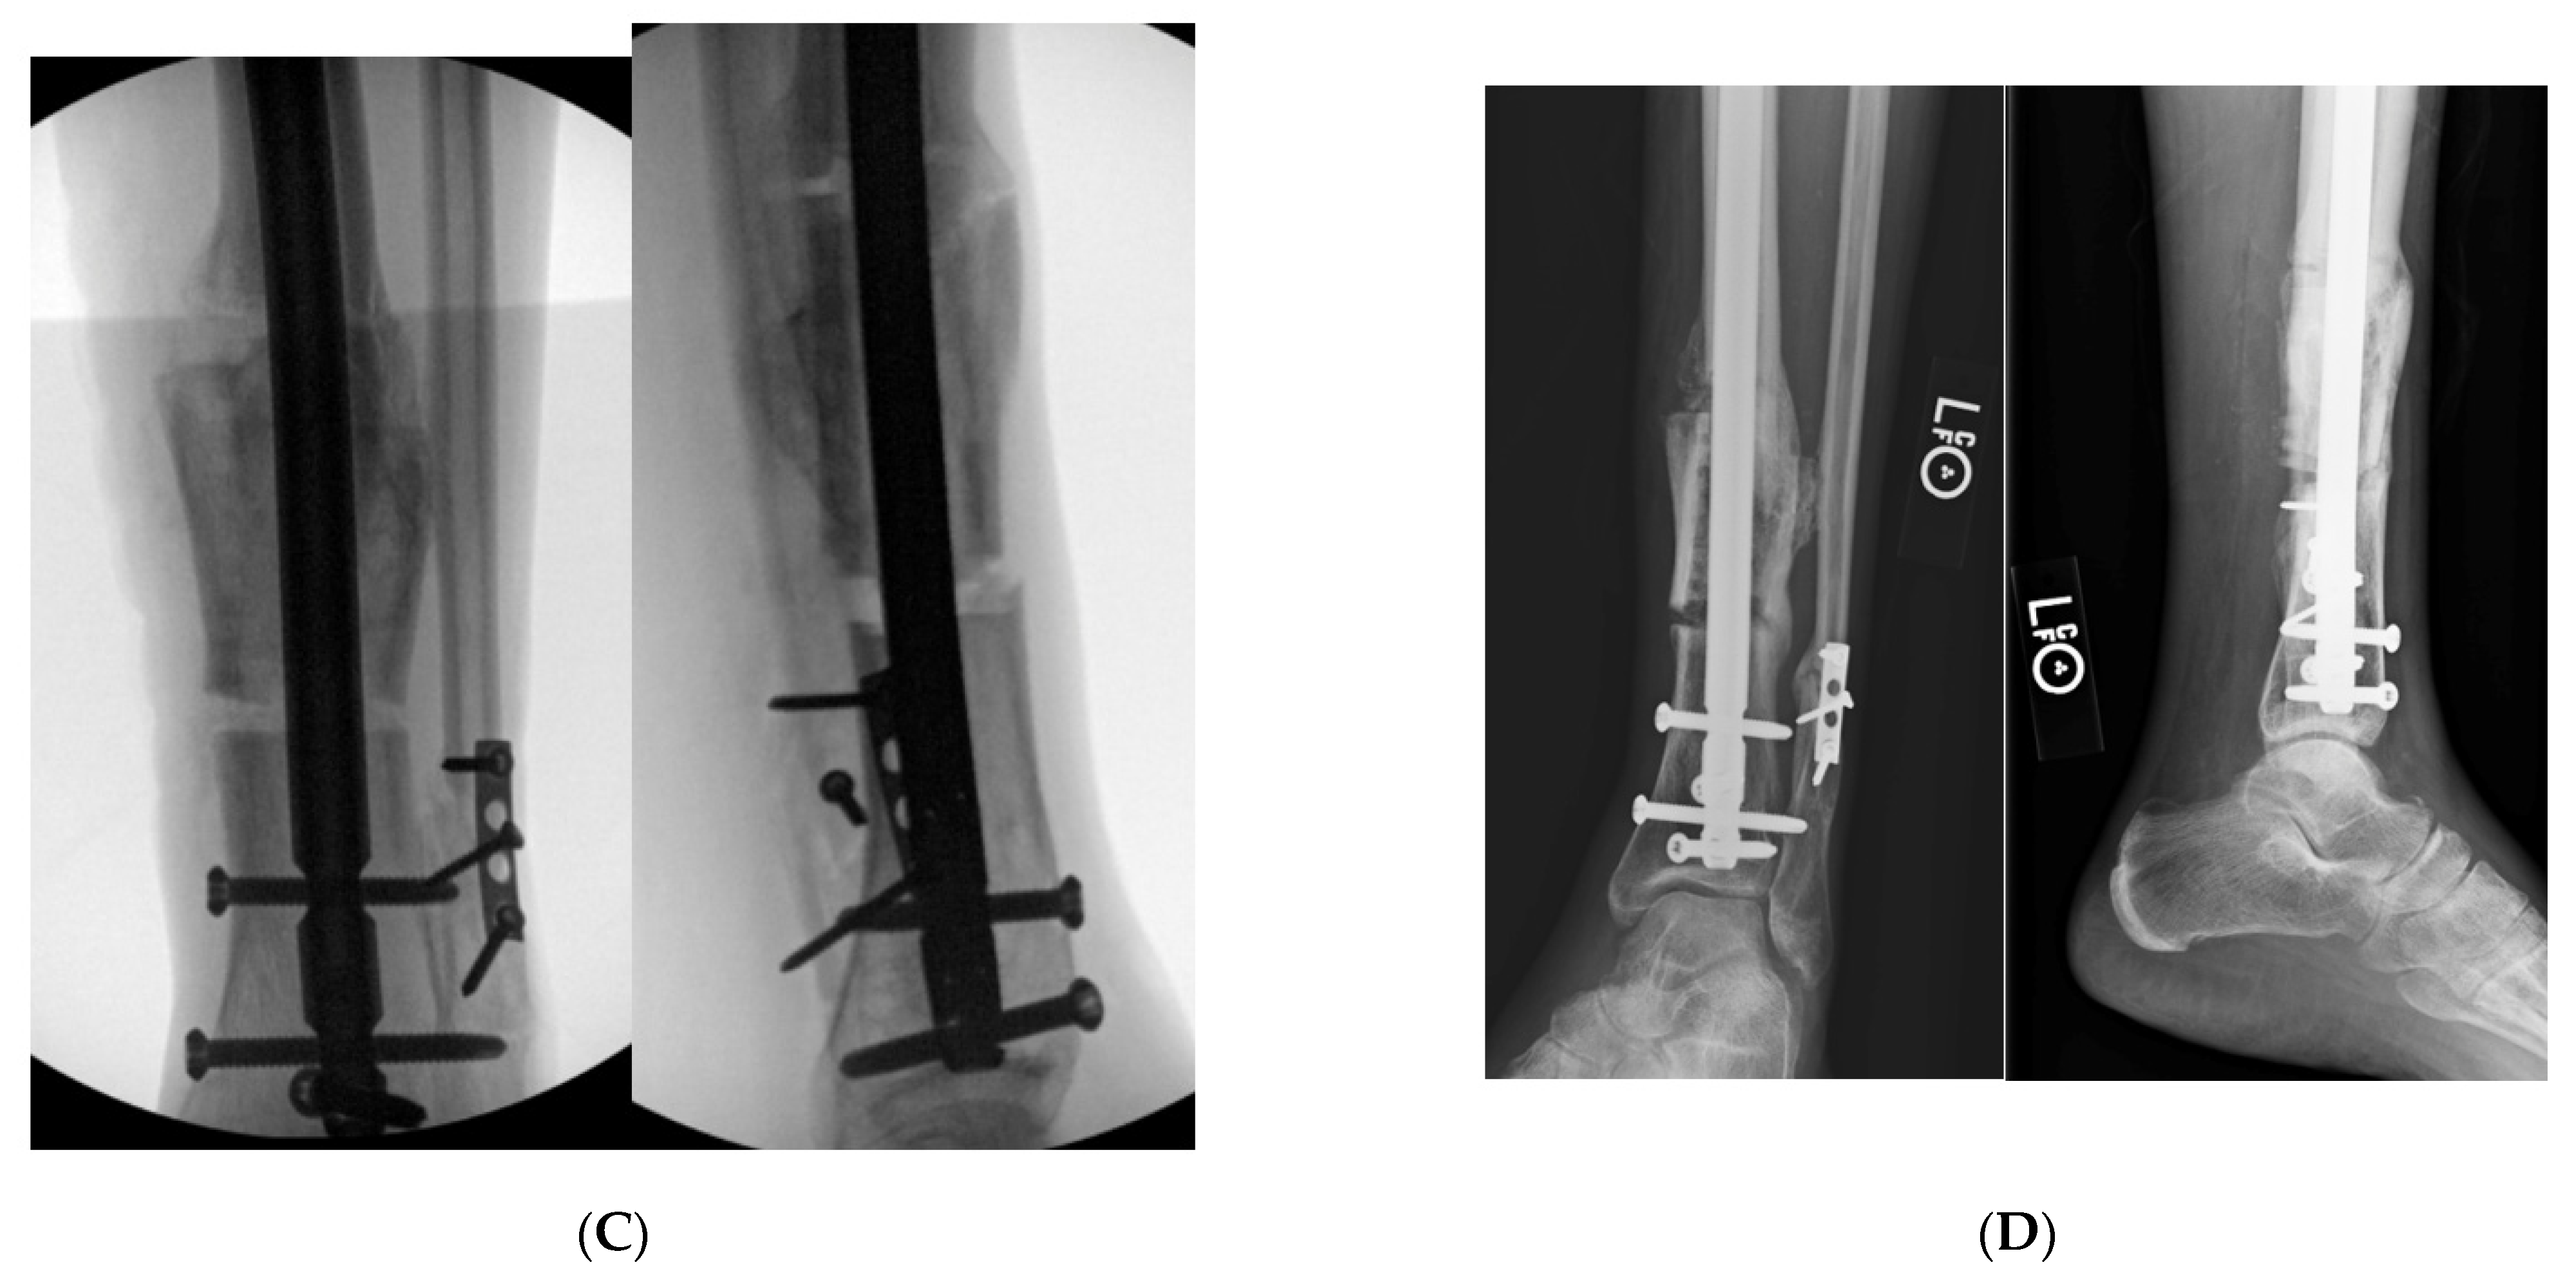

9.3. Case 3

Figure 6. (A): AP and lateral tibial XR demonstrating failure of tibial nail with valgus malunion. Notice there are not any distal interlocking screws. (B): Intraoperative fluoro views demonstrating medial universal distractor being used to assist with deformity correction, and maintain alignment during intramedullary nailing. (C): Intraoperative views demonstrating tibial nail and fibular plate after clamshell and fibular osteotomies. (D): AP and lateral 3-month post operative follow up XRs demonstrating healed clamshell osteotomy.